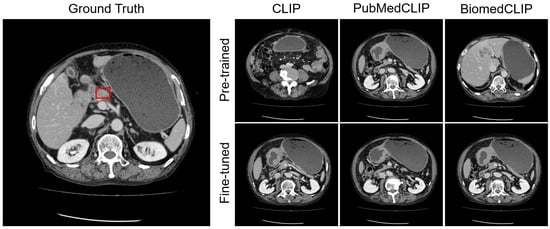

4.4. Visualization

Appendix C. Visualization

Appendix C.2. Organ Awareness